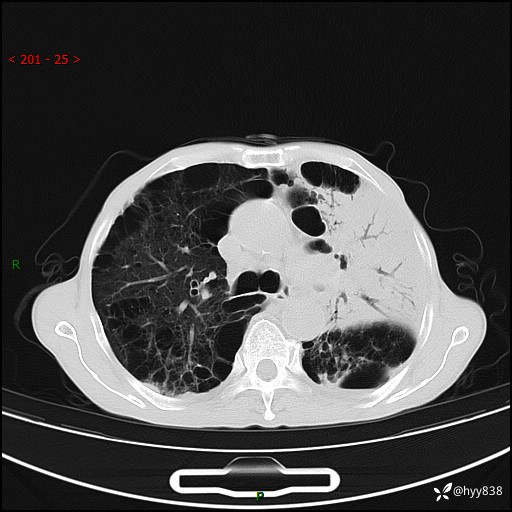

老年男性,反复咳嗽、咳痰、气喘10余年,再发3天。大叶性实变+胸膜病变-结果公布

主诉:反复咳嗽、咳痰、气喘10余年,再发3天

现病史:患者于10余年前开始出现反复咳嗽,咳痰,偶有少许黄色粘痰,伴活动后气喘,多于受凉及天气变化时发作,无胸痛、心悸、咯血等症状,休息后可自行缓解,起初因症状轻微可耐受,未到医院诊治,后症状逐渐加重,频发活动后气喘,活动耐力逐渐下降,未予药物治疗。3天前患者腹泻后出现气喘加重,伴咳嗽,咳黄色粘痰,痰较多,不易咳出,食欲差,无发热,无头昏、乏力、心慌,无头痛、晕厥,无端坐呼吸,无咯血,无胸痛、腹痛,无下肢水肿等,为求进一步诊治,来我院,急诊以“慢性阻塞性肺疾病伴急性下呼吸道感染”收入我科。 本次急性发作以来,患者精神、食欲差,大小便如常,体力下降。体重无明显变化。

胸部CT平扫+增强